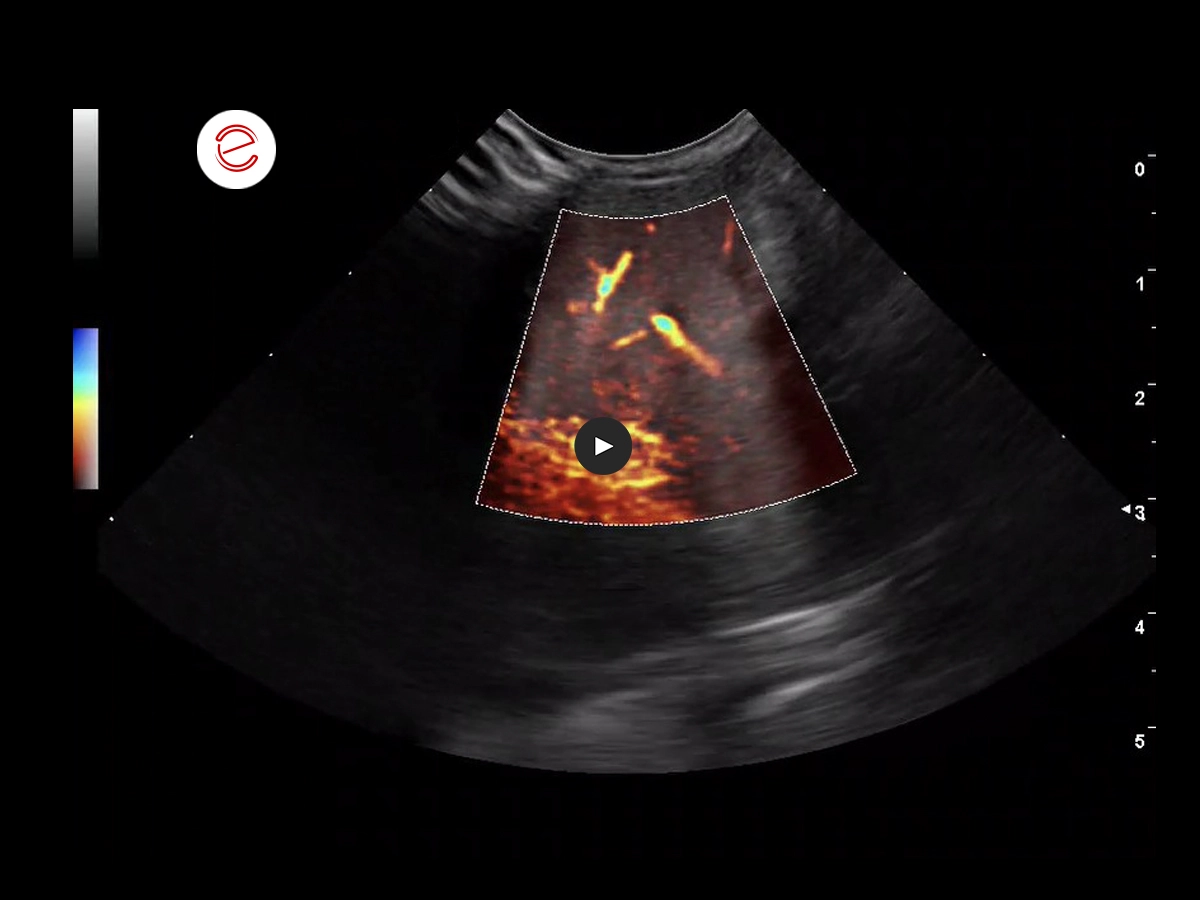

2 months before the respiratory issues: the larger right liver lobe is visible in the sagittal ventromedial view. The liver appears dense and heterogeneous, and the small hepatic vessels appear compressed.

The microV function outlines the compressed vessels.

Histopathology from an endoscopy-guided liver biopsy revealed liver fibrosis.